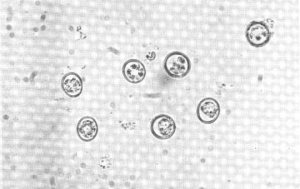

Телязиоз – глистное заболевание глаз (конъюнктивы и роговицы) и слезно-носового канала. Болеют им крупный рогатый скот, реже лошади, иногда свиньи и собаки. Очень редко — кошки. Протекает в виде энзоотии. Возбудитель – нематоды Thelasia rhodesi (чаще распространена на западе), Thelasia gulosa (на востоке), Thelasia skrjabini (на востоке и юге).

Это паразиты (глисты), которые паразитируют в субконъюнктивальном пространстве, вызывая воспаления, язвы роговицы и другие поражения глаза. Заболевание опасное и может вызвать даже потерю глаза у животного. В первую очередь необходимо ликвидировать паразитов. А ликвидацией нанесенного ущерба глазам должен заняться квалифированный офтальмолог.